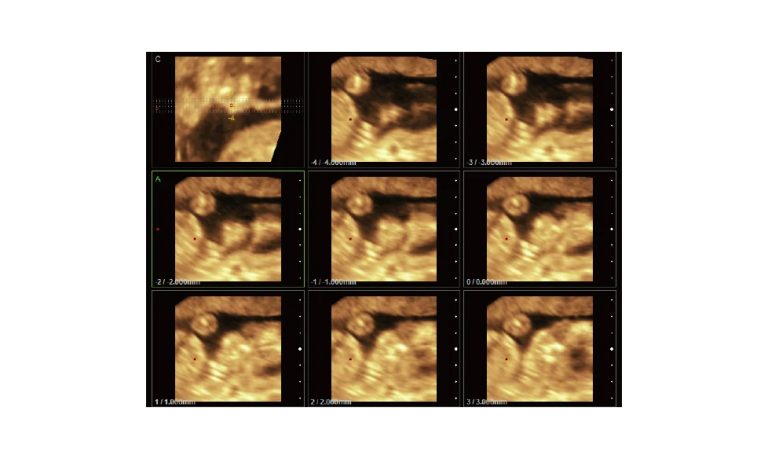

Ultrasound

Wide range of Ultrasound machines that suites a variety of applications from abdominal to rectal scans, we take in consideration how the world is moving towards mobility and mobile applications.

SonoScape Pro Pet E11

Smart Imaging

Introducing the first portable ultrasound with the C-Field+TM platform, redefining diagnostic imaging. Designed for veterinarians, it delivers unmatched clarity, ultra-fast processing, and seamless adaptability for all species. Experience Smart Imaging, Heartfelt Care—anywhere.

Equipped with cutting-edge veterinary software and optimized workflows, it embodies our commitment to Smart Imaging, Heartfelt Care – Wherever Their Journey Leads, with unparalleled performance and adaptability, this innovative system empowers veterinarians to provide exceptional care across all diagnostic applications,